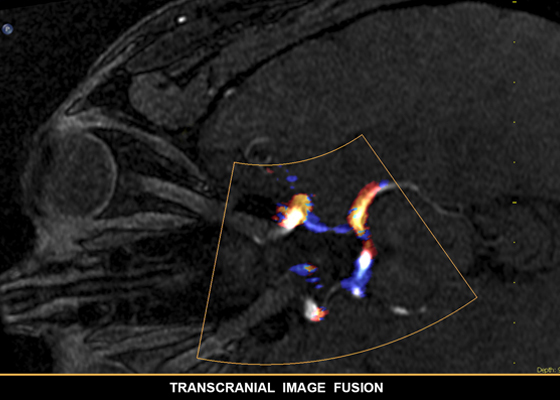

EchoNavigator: объединение рентгенографии и эхографии в режиме реального времени

Более глубокое понимание и уверенность при поиске и устранении проблем с помощью SmartFusion. EchoNavigator автоматически объединяет трехмерную чреспищеводную эхокардиографию и рентгенографию в режиме реального времени, чтобы вы могли интуитивно направлять свое устройство в трехмерном пространстве с более высокой скоростью.